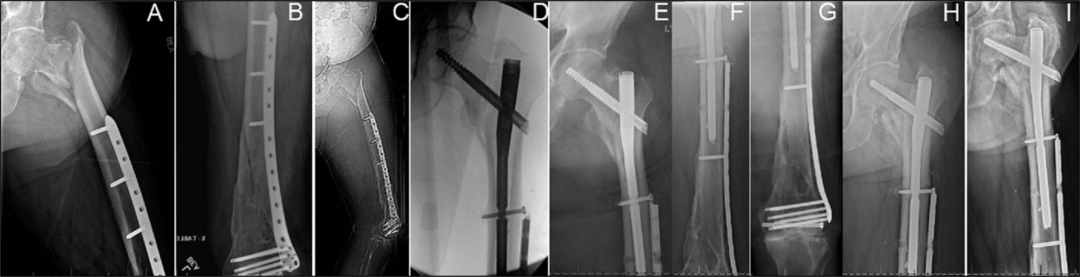

存在无法移除或不打算移除的远端股钢板(图)。

考虑到远端骨折延伸,使用短钉是不合适的,而由于远端髓内植入物的存在,不能使用长钉。

外侧壁骨折的存在是骨折内翻塌陷的潜在危险因素,特别是对于股骨髓腔较大的患者,在这些骨折中,较长的钉可能是首选(图)。